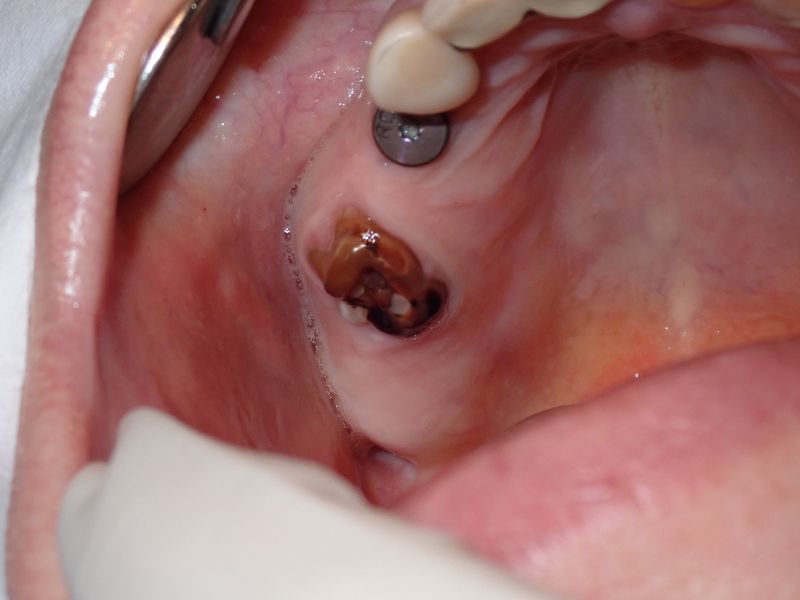

fredlibc | profile | all galleries >> Galleries >> ARumiantsava - immediate 16 tree view | thumbnails | slideshow

PC060009.JPG (1 of 4)